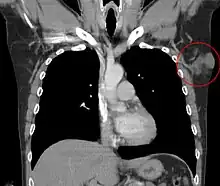

Additional images

- Subcutaneous tissue infiltration (i.e. "honeycomb" growth pattern)